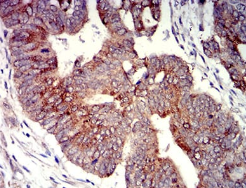

P2RY4 Mouse Monoclonal antibody[3B4C1]

Species Reactivity :   Human

IHC    1/200 - 1/1000